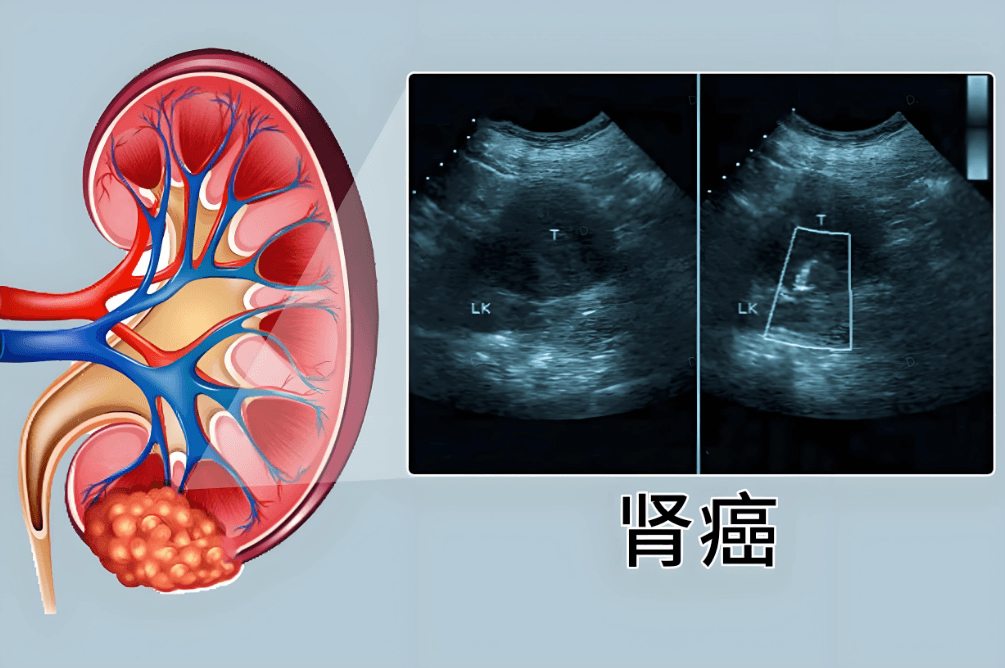

肾细胞癌(RCC)占肾脏恶性肿瘤的90%,作为为肾脏最常见的恶性肿瘤类型之一,2022年全球新发病例超43万(WHO数据)。传统治疗方案存在明显局限: